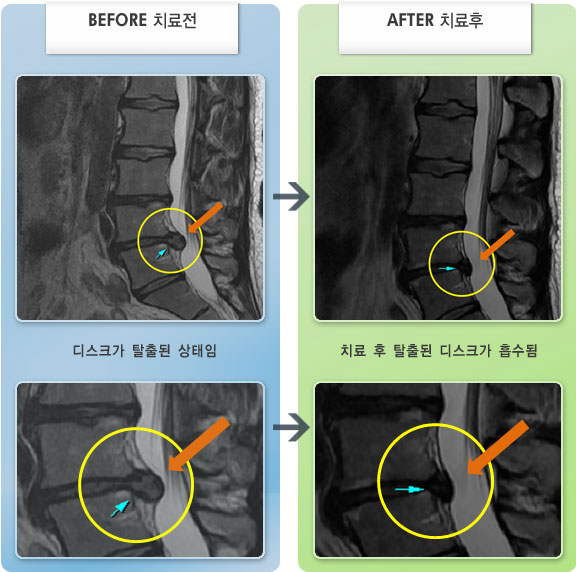

Before

After

허리와 양쪽 엉덩이 통증 및 좌측 둔부, 대퇴, 소퇴 후면부 통증 및 저림

2013.05.14 ~ 2014.04.23